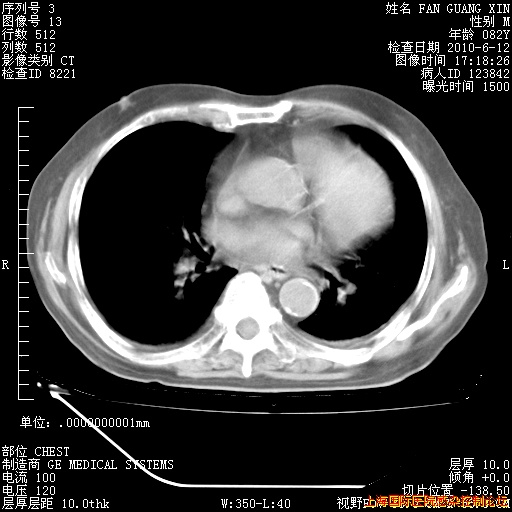

6月12日纵膈窗

整整相隔30天的肺部CT好像有所好转啊。甲强龙减量第3天,需要观察体温。